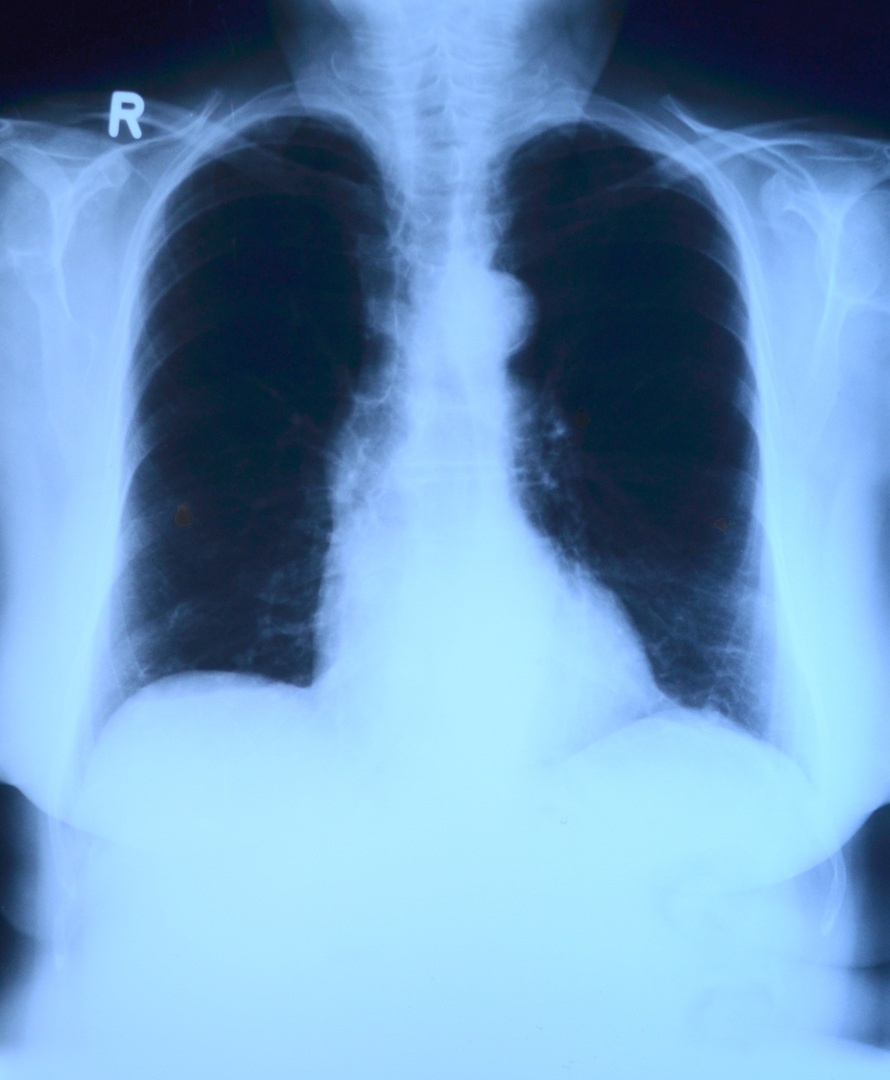

Не хуже профессиональных рентгенологов: ИИ обучили анализу снимков легких

Фото с сайта pxhere.com